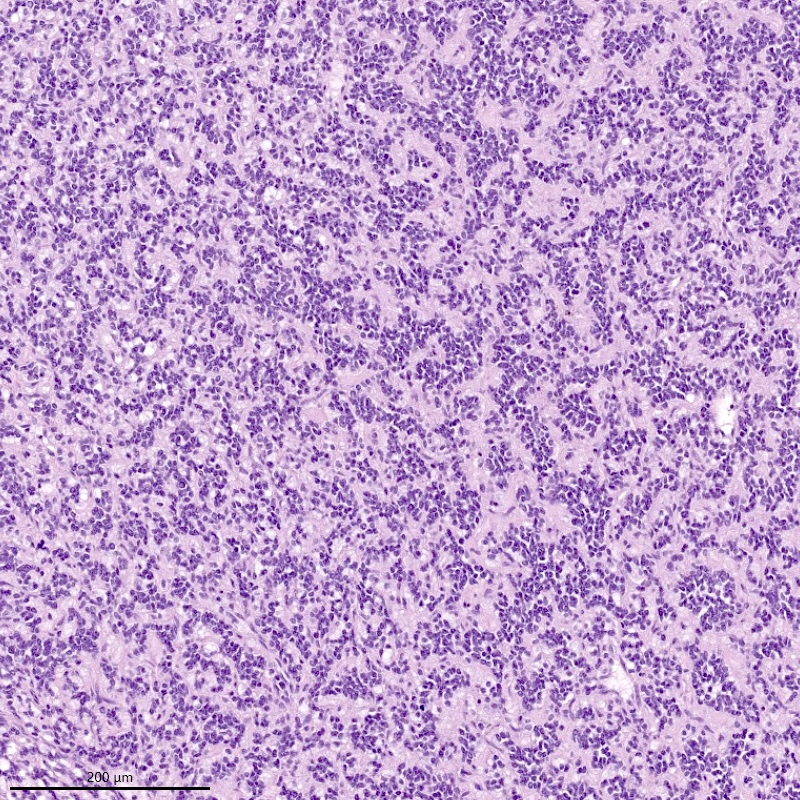

Microscopic (histologic) description

- Irregular cellular islands, forming permeative tongue-like pattern of myometrial invasion with frequent vascular invasion

- Monotonous oval to spindle cells with minimal cytologic atypia, vesicular chromatin and scant cytoplasm

- Mitotic count is usually low (< 5/10 high power fields), necrosis is usually absent

- Tumor cells may whorl around delicate arteriolar type vessels, reminiscent of proliferative phase endometrial stroma

- May have admixed collagen bands / plaques and foamy histiocytes

Microscopic (histologic) images

Contributed by Elizabeth Kertowidjojo, M.D., Ph.D., M.P.H. and Ayse Ayhan, M.D., Ph.D.